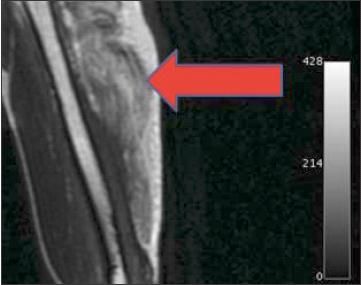

Figure 3 –

A severe strain of the long head of the triceps is demonstrated here by the increased signal intensity on the MRI scan (arrow).

MRI may be a more sensitive measure because of sonographer experience. It may be helpful if the diagnosis is unclear, if physical examination findings are out of proportion to the mechanism of injury or objective findings, or if it is important to quantify injury severity in a high-level athlete (Figures 2 and 3). Hematoma and interstitial edema are well visualized on T2- weighted images. MRI also may be helpful in the evaluation of complete tears with tendon retraction for surgical decision making.